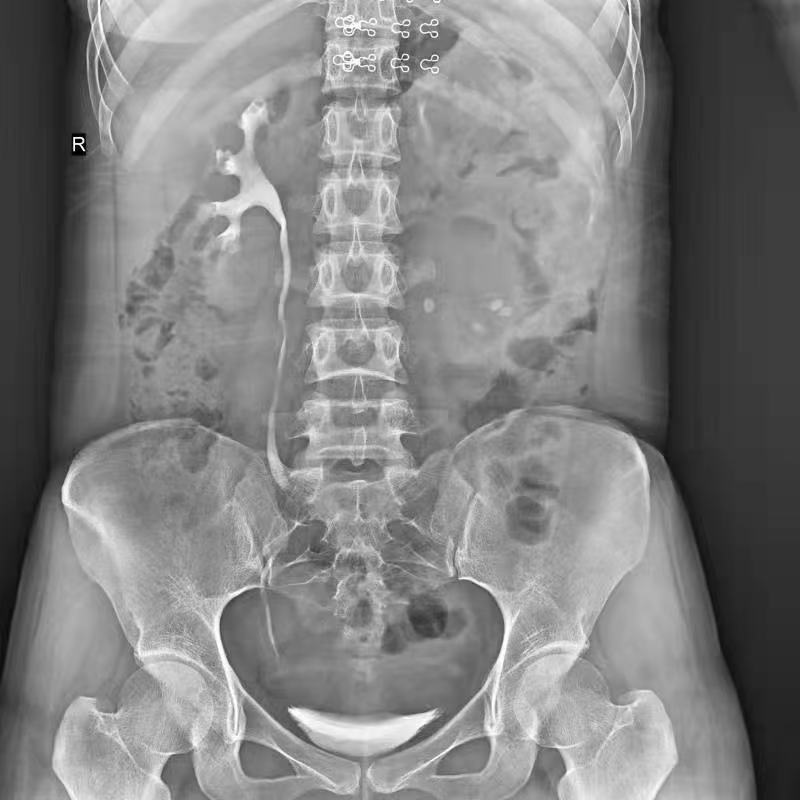

普利德醫療自主研發的新一代數字化X線透視攝影系統,可應用于DR攝影、數字透視、數字造影以及可視化精準DR拍片等多種臨床X線檢查領域。

● 17*17英寸的超高清像素動態平板探測器,更大的視野范圍,無需移動即可觀察整個動態過程,避免拖尾、噪聲對圖像的影響;

● 高效動態平板技術,圖像不會有幾何畸變,提供高分辨率和精確的圖像,為醫生臨床診斷提供精準依據;

● 最高幀速可達30幀/秒,動態采集清晰流暢,避免漏診、誤診情況的發生;

● 在可視過程或回放過程中,如發現疑似病灶,可進行毫秒級高清點片,隨時抓取單幀圖像,精準捕抓病灶。